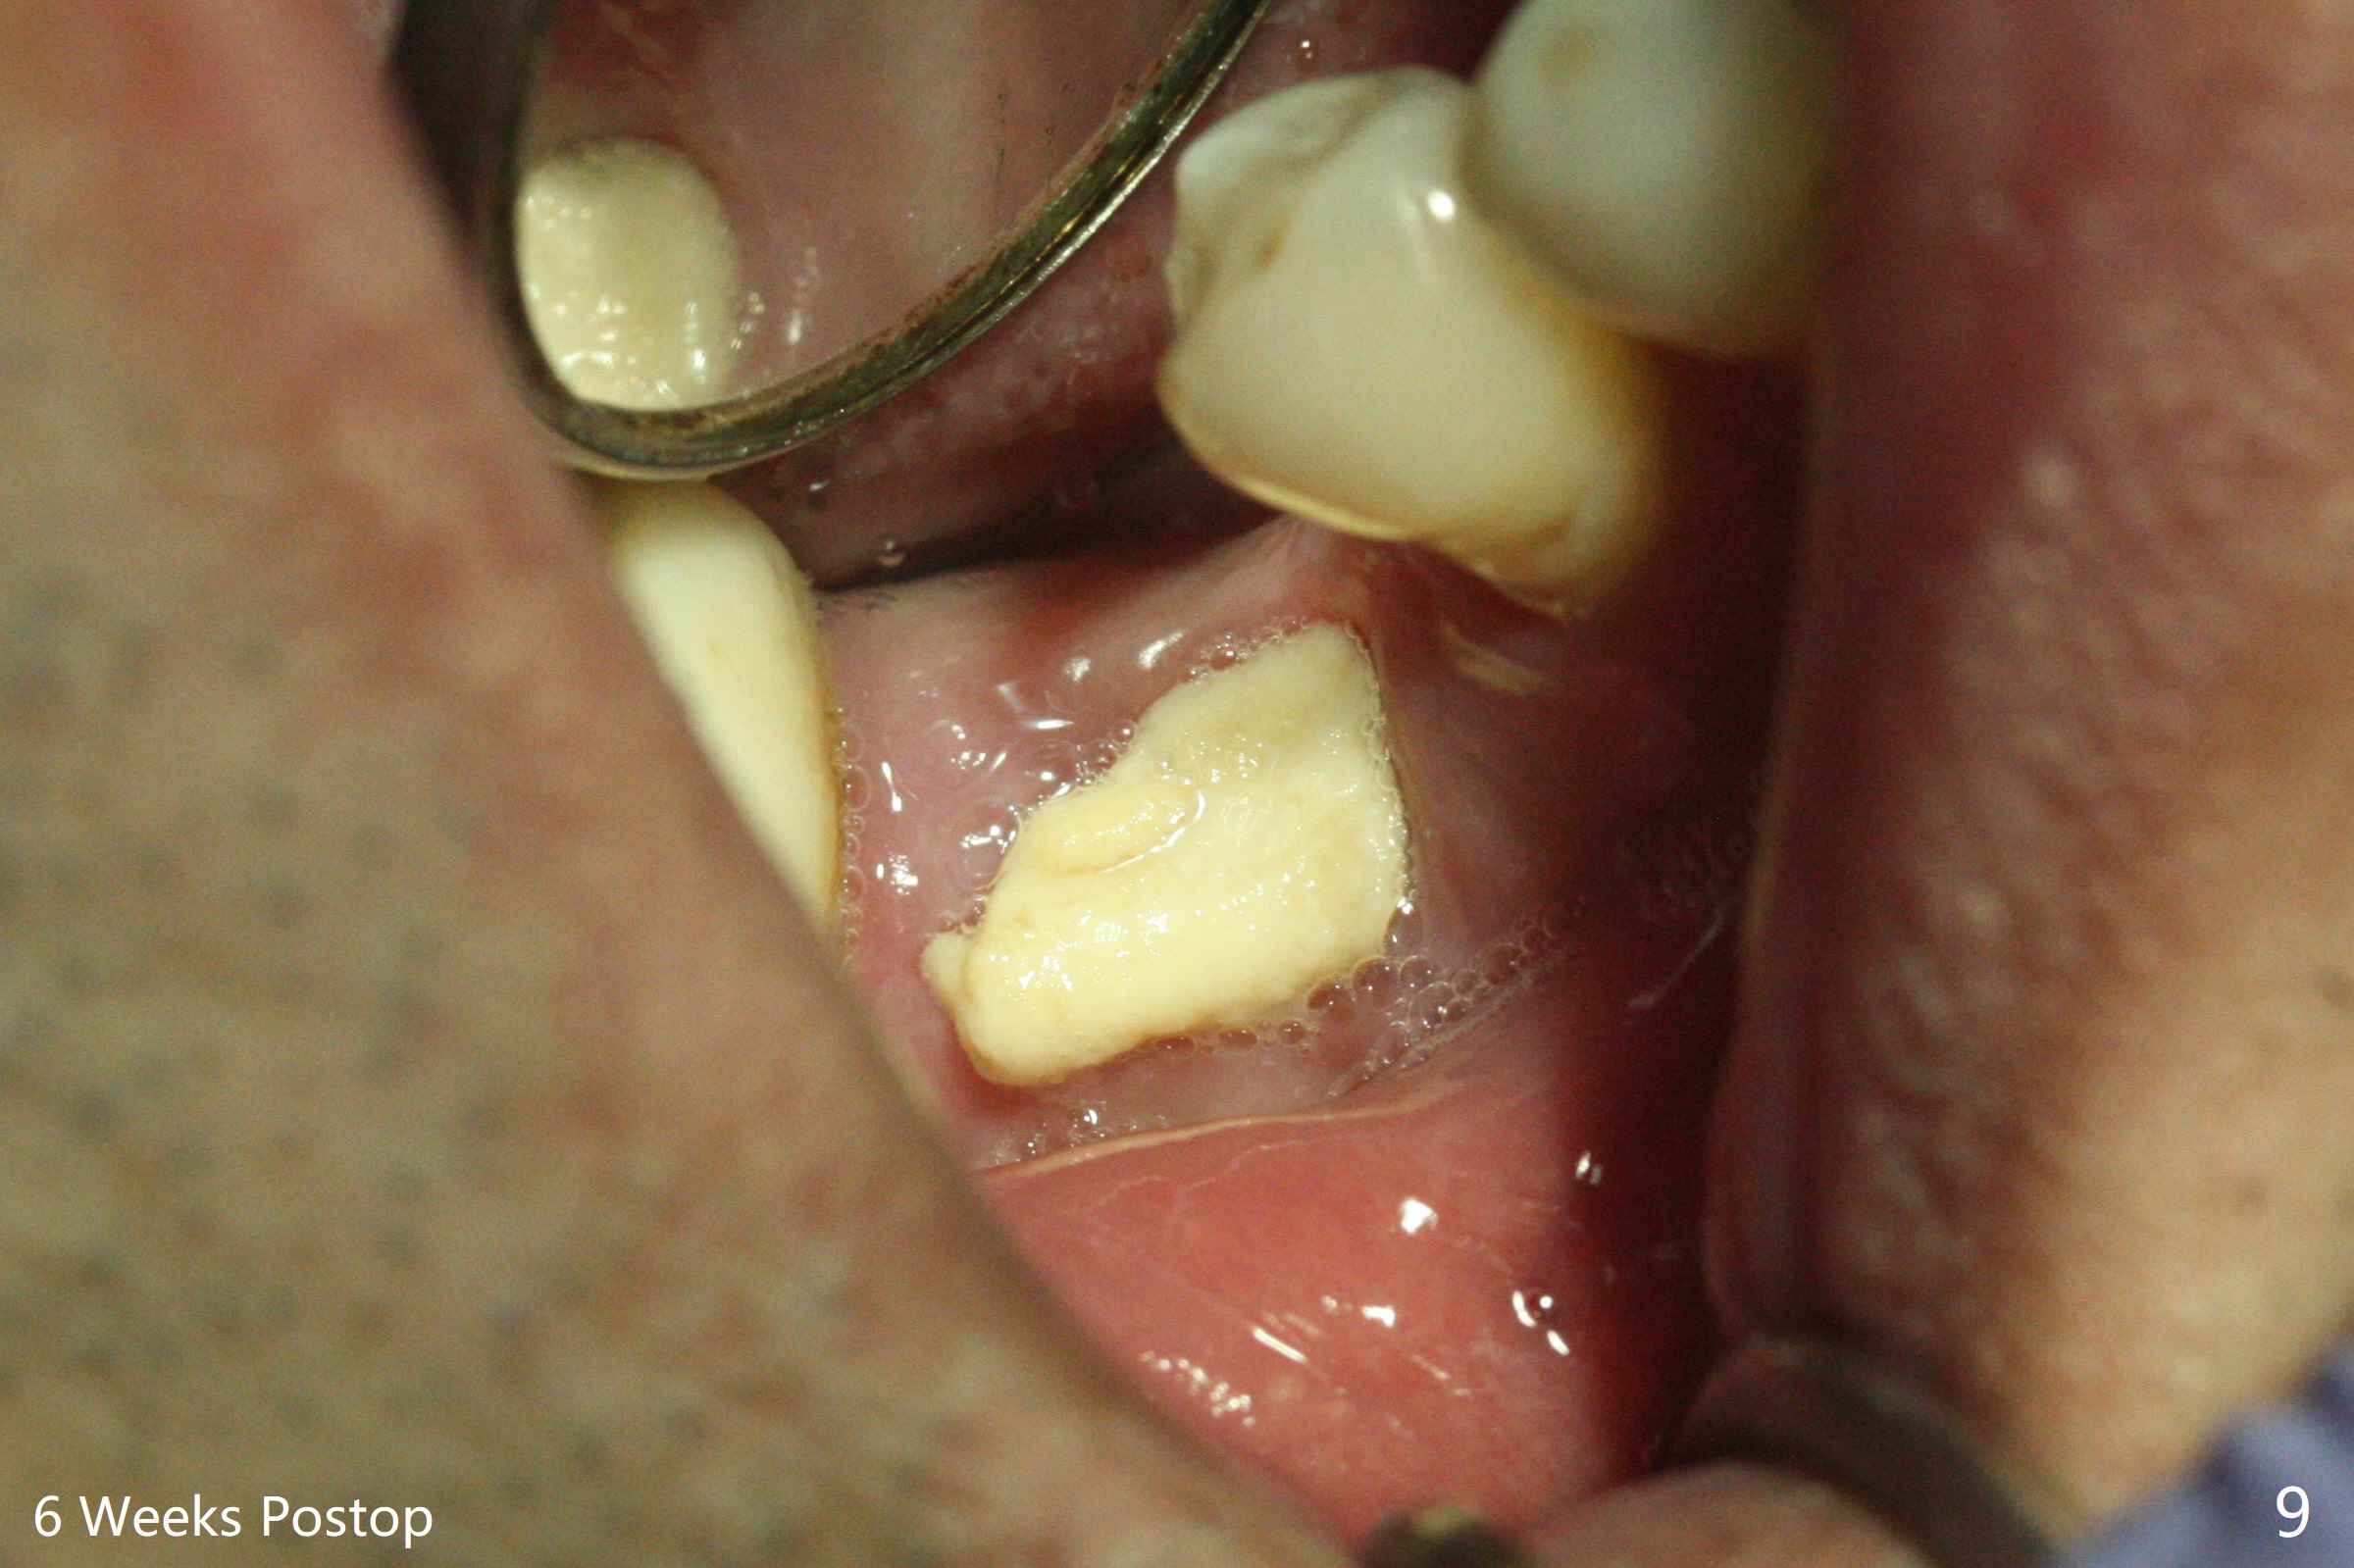

In spite of use of water pik, the coronal threads of the implant at #30 remain exposed 2 months postop (Fig.1). Envelop incision with mesial and distal accessory release ones reveals buccal bony defect (Fig.2). After 2nd spin (1500 RPM for 10 minutes), PRF forms in the red tube (Fig.3 yellow gel-like). Following use of Titanium brush, sticky bone is place (not so bone block-like, Fig.4), followed by a large piece of PRF membrane (from the red tube of Fig.3), Cytoplast (Fig.5,6 white porous) and a small piece of PRF membrane (from the white tube, next to the thin gingiva). The distal (Fig.6 D) and mesial (Fig.7 M) flaps are approximated (arrows without suture) as much as possible as well as lingual. 4-0 Polyglycolic Acid suture is used. Periodontal dressing dislodges 5 days postop. When the patient returns 1 week postop, he is pain free. Although Cytoplast is exposed, the surrounding gingiva seems to be healthy (Fig.8). Later the permanent crown of #31 is temporarily cemented with OHI. It appears that Cytoplast could be used to cover PRF membranes for soft tissue defect, followed by immediate provisional at the stage of immediate implant. The discolored (apparently contaminated) Cytoplast seems to be expelled 6 weeks postop (Fig.9). When the latter is removed, the soft tissue looks normal (Fig.10). Two weeks later, the apparently normal, but thin gingiva forms over the former granulation tissue (Fig.11 *, as compared to Fig.10). There is not enough bone coronal to the implant plateau 2 months post graft (Fig.12). Three months later, bone graft will be re-placed possibly with uncover.